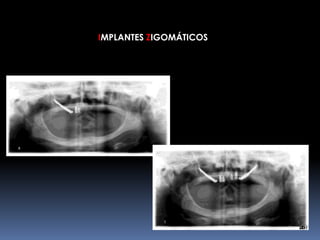

IMPLANTES ZIGOMÁTICOS     INDICAÇÕESMaxilar Edéntulo com Grande Reabsorção óssea		Pneumatização do Seio Maxilar	Status Pós-Maxilectomia	Fenda Lábio-Palatina

IMPLANTES ZIGOMÁTICOSFRACASSO FACIALHipoplasia maxilarFalso prognatismo